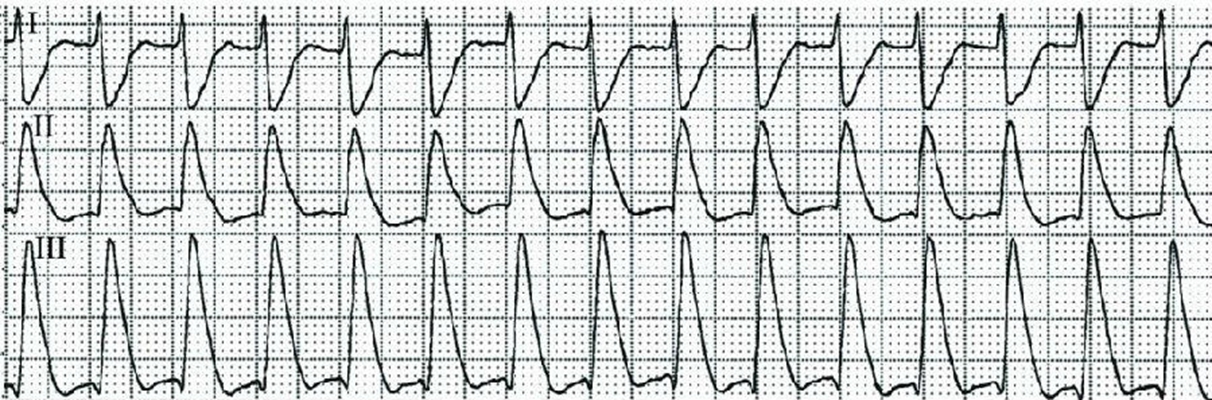

預激綜合症圖片

預激綜合徵心電圖 (79)

預激綜合徵心電圖 (8)

預激綜合徵心電圖 (80)

預激綜合徵心電圖 (81)

A:預激綜合徵典型的心電圖表現是竇性心搏的PR間期縮短,短於0.12s,而且導聯的QRS波群時間超過0.12s。QRS波群起始部分會有粗鈍,終末部分正常,甚至會導致ST-T波型呈現繼發性的改變,甚至於QRS波群主波方向相反。預激綜合徵是指心房……

A:預激綜合徵是很少見的心律失常,是房室傳導異常的一種類型,提早興奮心室的一部分或全部,引起心室肌提前激動,常合併室上性心動過速。心電圖可見PR間期縮短小於0.12秒;QRS時限延長0.11秒以上;QRS波群起始部粗鈍,繼發性ST-T改變。沒有……

A:預激綜合徵的定義是:因為心房和心室之間存在著異常傳導通路,使部分電活動從心房經過這個通路傳導到心室,引起心室局部心肌細胞發生提前除極,在心電圖上可以出現預激波,這就是預激綜合徵。有預激綜合徵的患者會因這條特殊通路的存在,導致電活動在心房心室……